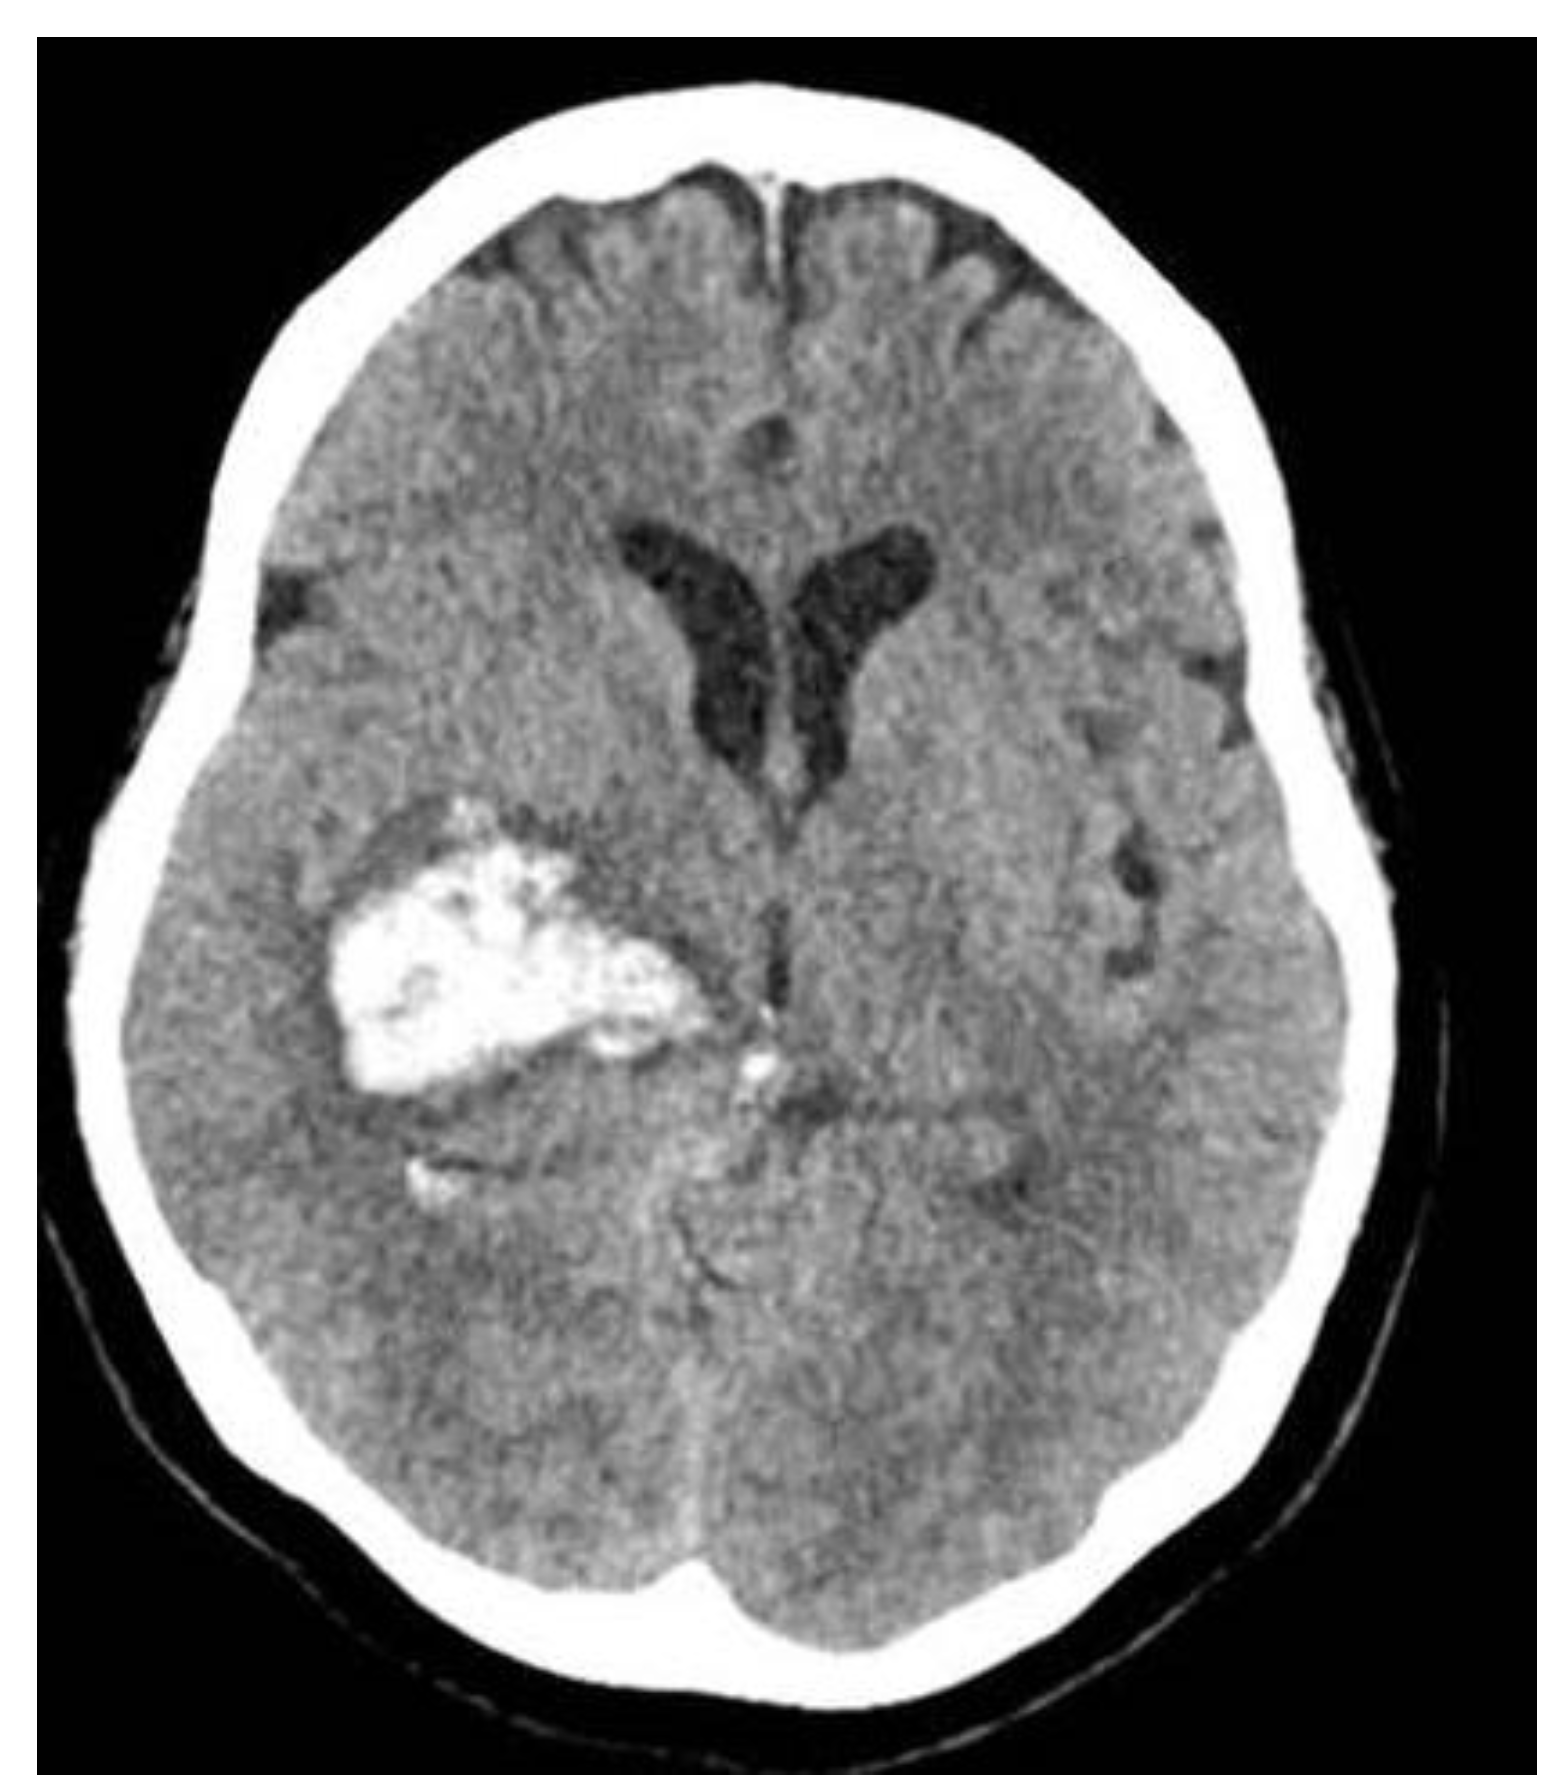

A 48-year-old woman with no significant past medical history presented to the local emergency room after experiencing acute onset severe headache and then left-sided paralysis. Computed tomography (CT) showed large right basal ganglia hemorrhage (Figure 1). The patient experienced rapid decline in mentation and was urgently intubated and transferred to the University of Maryland Medical Center. Given the midline shift, an emergent left frontal EVD was placed. Four days later, her course was complicated by ventilator-associated pneumonia with methicillin-susceptible Staphylococcus aureus (MSSA) that was treated with intravenous cefazolin 2 grams every 8 hours for 7 days.

Figure 1.

Right sided intraparenchymal hemorrhage (4.2 x 2.3 cm) with 6 mm midline shift towards the left and intraventricular extension into the right lateral ventricle.